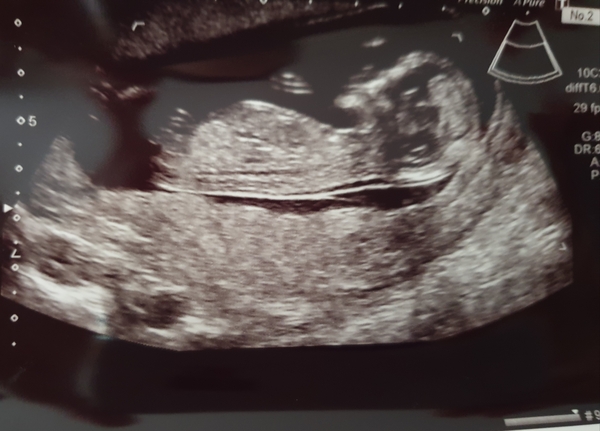

Chuchu14 · 22/07/2019 08:04

Congratulations on the boys @DaisyMay25 and @FirstTim3Mummy!

@Bentley111glad you are feeling better. It's nice when the sickness starts to fade and you get more energy.

Here's our little bubba didnt have time to post a picture the other day Smile